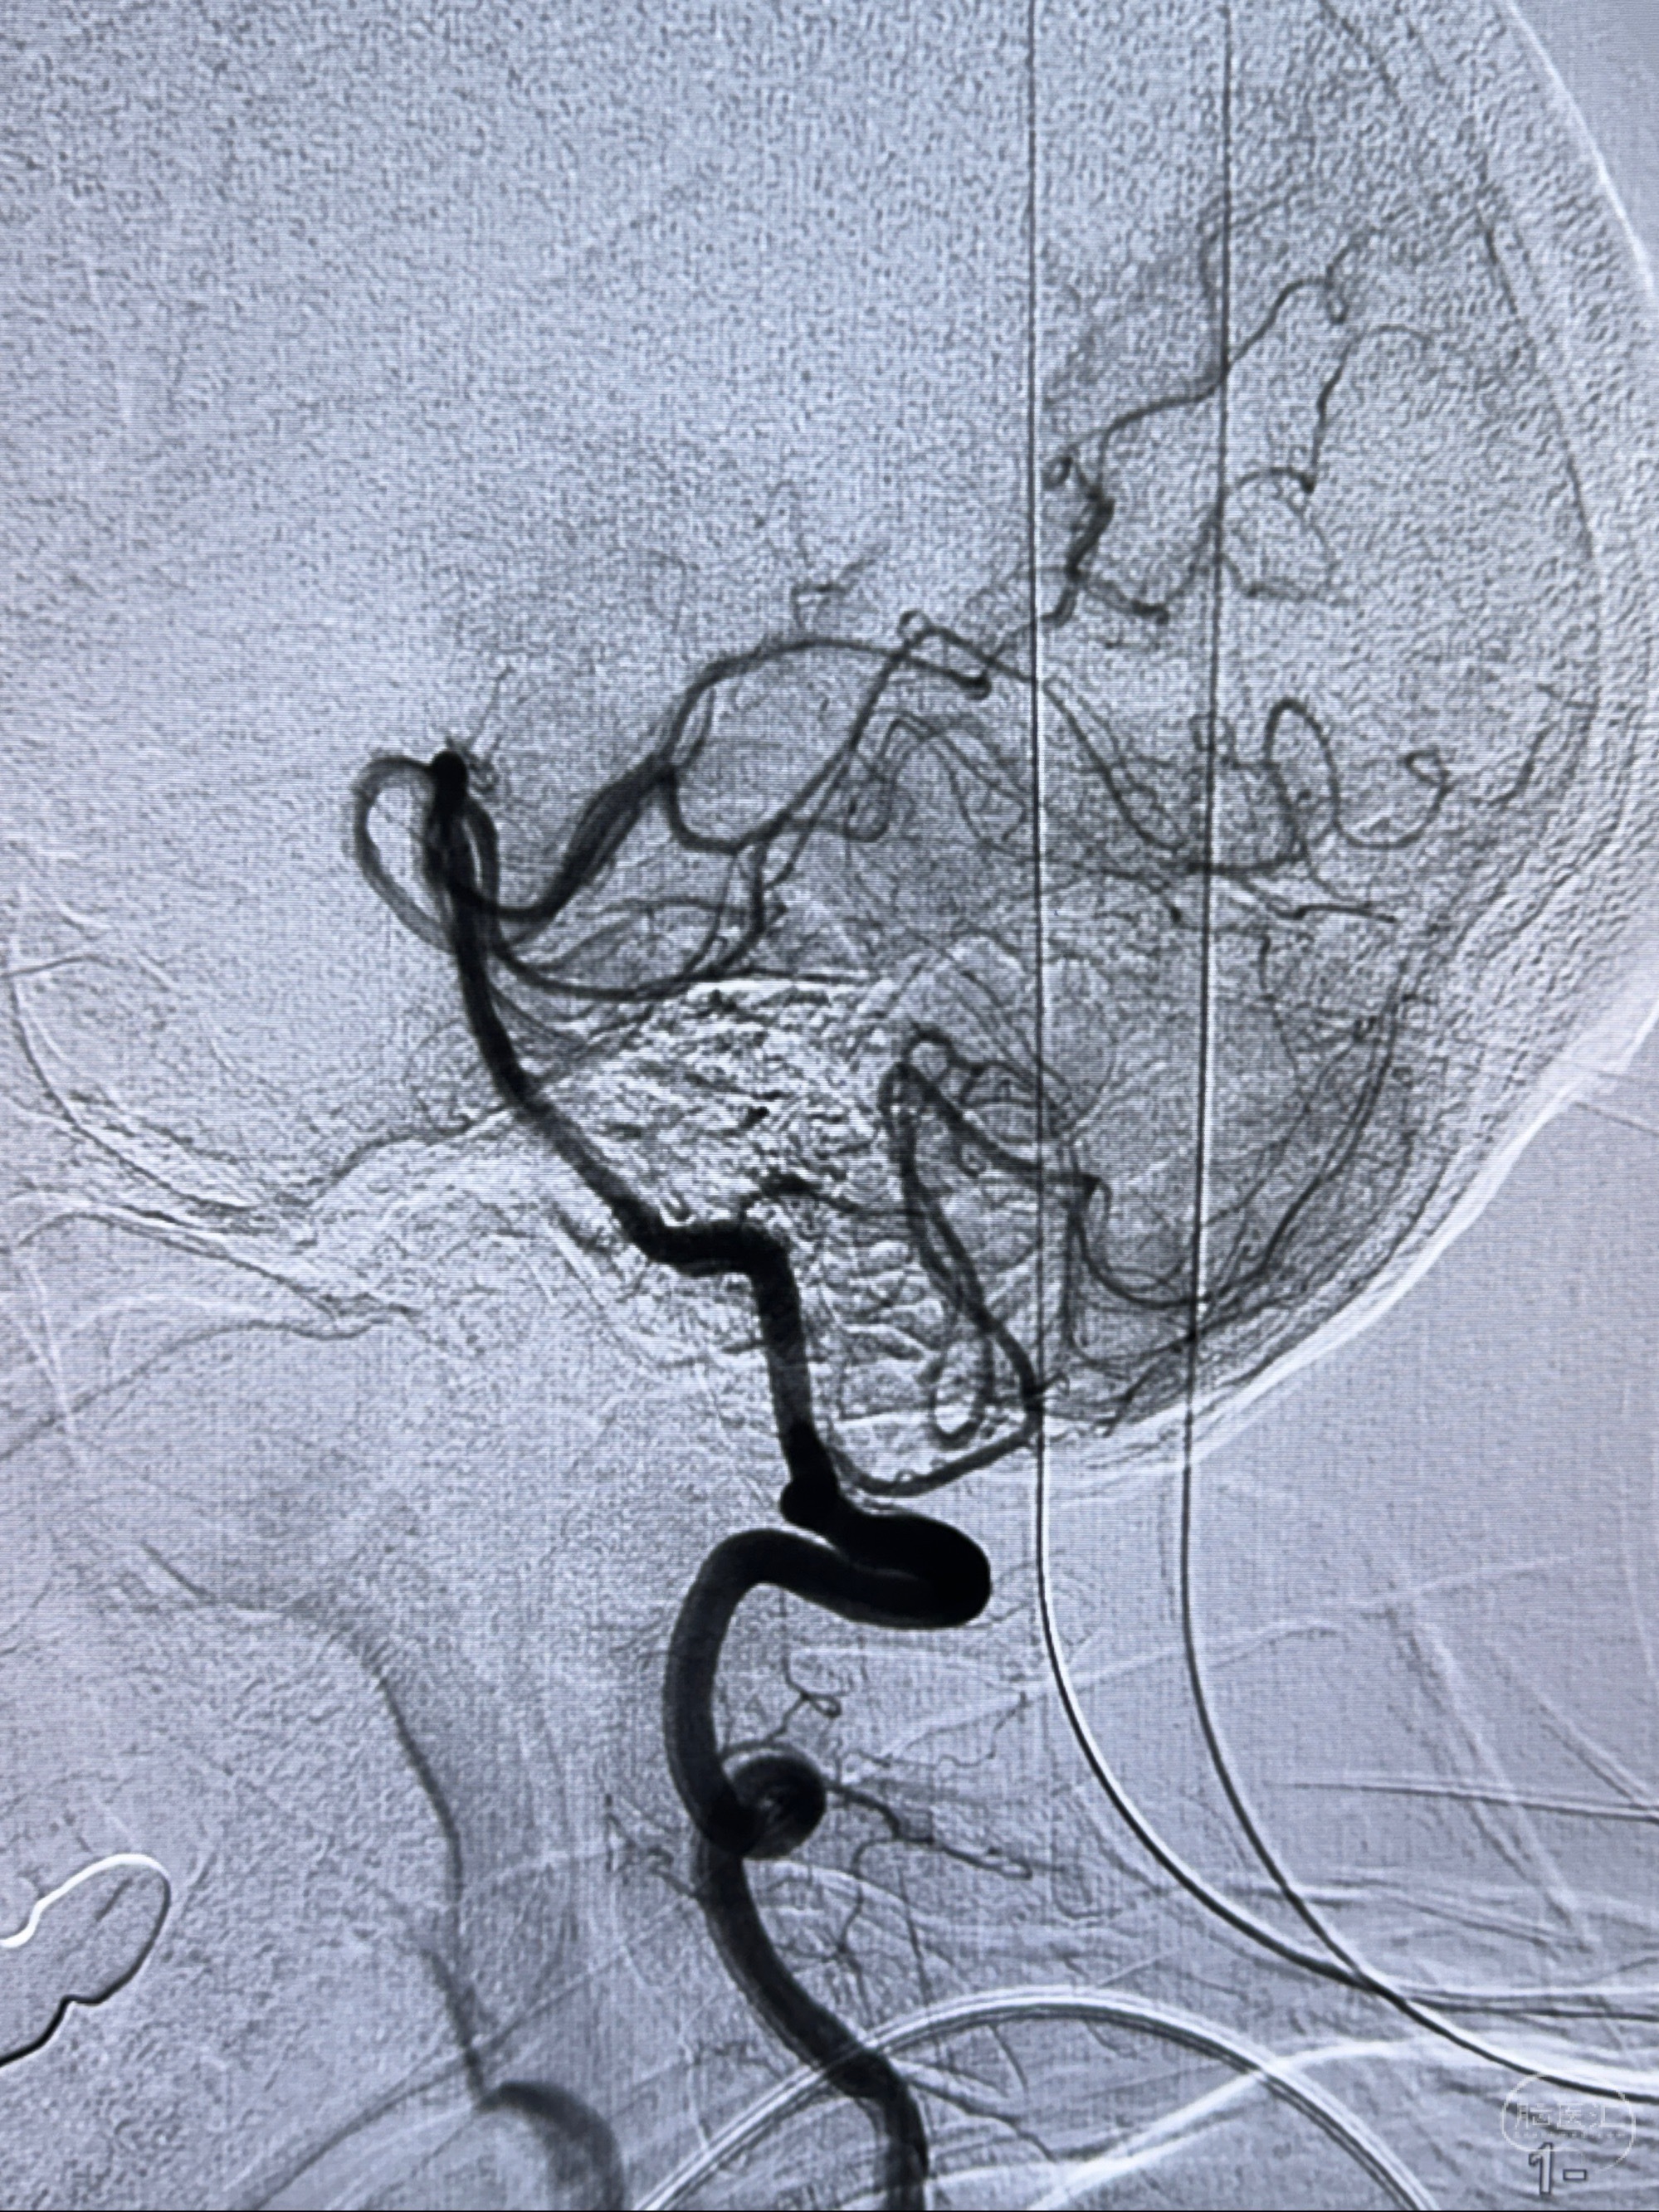

2023-11-24DSA:右侧大脑中动脉下干起始部动脉瘤,约2.3*2.5mm,形态规则

2023-12-04全麻下行支架辅助治疗

S-AB4-20mm